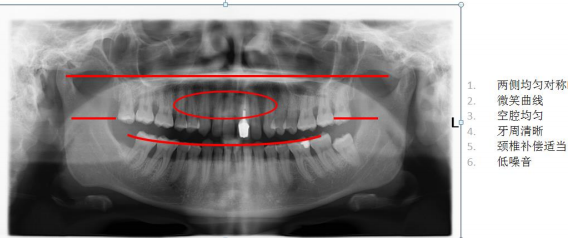

其他全景機(jī)前牙掃描層厚較窄,定位困難。 CRANEX CRA-2 前牙掃描層厚增加 50%,提高前牙區(qū)圖像質(zhì)量,定位精準(zhǔn) 成人全景:顯示上下牙列、牙槽骨、神經(jīng)管及 TMU,圖像均勻,前牙區(qū)結(jié)構(gòu)也可清晰顯示

結(jié)論:

前牙掃描層增厚技術(shù)與傳統(tǒng)的前牙掃描攝影技術(shù)相比,提高了病人前牙區(qū)圖像質(zhì)量,利用幾何學(xué)原理和 最佳的光束方向, 能產(chǎn)生連續(xù)的圖像, 掃描出清晰的上下頜骨.鼻副竇及顳下頜關(guān)節(jié)結(jié)構(gòu). 2) 高靈敏度 CCD 探測(cè)器: 高清 CCD 探測(cè)器,實(shí)現(xiàn)空間分辨率 6.25lp/mm 呈現(xiàn),清晰呈現(xiàn)細(xì)微結(jié)構(gòu)影像。 3) 窄光束技術(shù):采用 0.5mm 小焦點(diǎn),高性能準(zhǔn)直器 Slit beam 及小焦點(diǎn)技術(shù)使圖像高度清晰. 4) 獨(dú)特的高穩(wěn)定性 DC 反饋控制系統(tǒng): 曝光時(shí)如果輸入電壓有所波動(dòng), 采用 DC 反饋控制系統(tǒng),使 X 線球管電 壓及電流保持恒定. 5) 具有曝光脊椎自動(dòng)補(bǔ)償功能, 可減少脊椎及頸部贅肉對(duì)圖像的影響,而不影響圖像其他部分.從而提高圖像的 清晰度. (二) 快速全景掃描,減少移動(dòng)偽影,提供最佳圖像質(zhì)量和最低劑量 ? 快速全景掃描提供極佳圖像質(zhì)量 ? 成人快速掃描僅需 9 秒 ? 兒童快速掃描僅需 8 秒 ? 僅需三步,即可快速完成操作 (三) 定位最精準(zhǔn),拍攝最便捷 1) 依靠獨(dú)特的五點(diǎn)頭部定位系統(tǒng)及三光束定位系統(tǒng),實(shí)現(xiàn)準(zhǔn)確的三維立體定位. ? 三盞激光定位燈——定位準(zhǔn)確 ? 專利技術(shù)五點(diǎn)頭顱定位裝置,定位穩(wěn)定 ? 開放式設(shè)計(jì) 2) 直觀的控制面板 (四) 智能投照選擇及劑量控制技術(shù)——操作者不需選擇任何攝影條件就可以實(shí)現(xiàn)精準(zhǔn)掃描 ? 專利的自動(dòng)曝光劑量控制(AES),根據(jù)頭部定位支架所測(cè)量的病人頭部寬度,自動(dòng)調(diào)節(jié) KV 值,通 過智能曝光負(fù)反饋系統(tǒng),實(shí)現(xiàn)低劑量下的最精準(zhǔn)的曝光控制。 ? 自動(dòng)準(zhǔn)直器選擇(ACS),可以根據(jù)病人類型不同,拍攝范圍 FOV 不同,自動(dòng)選擇準(zhǔn)直器實(shí)現(xiàn)曝光 控制。 ? 自動(dòng)曝光控制(AEC),通過自動(dòng)感應(yīng)單元反饋電路,實(shí)現(xiàn)自動(dòng)曝光參數(shù)控制 ? 具有曝光脊椎自動(dòng)補(bǔ)償功能, 可減少脊椎及頸部贅肉對(duì)圖像的影響,而不影響圖像其他部分.從而提 高圖像的清晰度. (五) 結(jié)構(gòu)緊湊,完全不受機(jī)房空間限制 ? 僅 1.5*2 平方米的裝機(jī)面積即可滿足要求 ? 重量為 100KG, 重量大,穩(wěn)定性高 (六) 具有功能豐富發(fā)應(yīng)用軟件,可以進(jìn)行病例輸入、病例搜索、圖像放大、圖像增強(qiáng)、負(fù)像,長(zhǎng)度、密度、角度測(cè)量,進(jìn)行模擬種植等、可以進(jìn)入醫(yī)院的 PACS 系統(tǒng)。